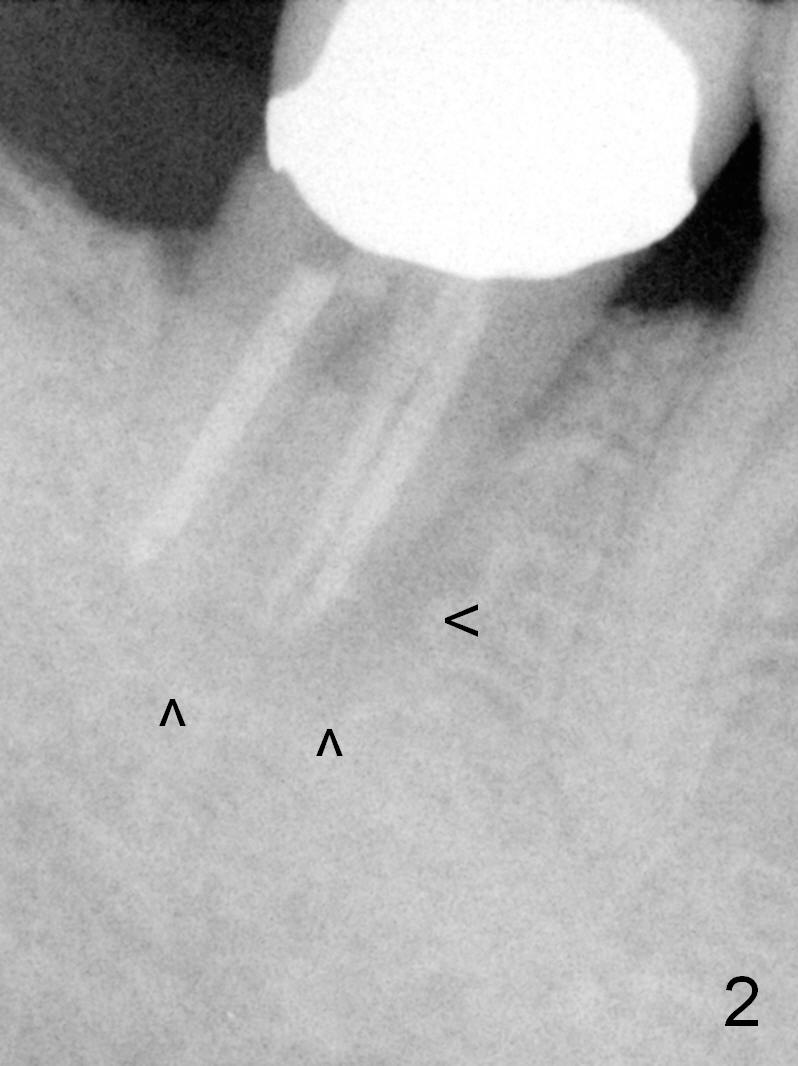

The 61-year-old man is nervous about dentistry. When he returns for #4 implant, he wants an implant at #31 first. Fig.1 shows #31 crown fracture after root canal therapy. Three years after crown placement, there is sign of mesial root fracture (Fig.2 arrowheads). Four years post extraction, bone height is 12 mm (Fig.3 parallel pin 10 mm). An extra wide implant is to be placed, since there is enough bone width. With infiltration anesthesia, the patient feels pain when a 5.4x10 mm drill is being used, 1 mm short of the desirable depth (Fig.4). After Inferior Alveolar Nerve block, the last drill reaches the depth. A 5.9x10 mm implant is placed with insertion torque 50 Ncm (Fig.5 I). A 7.8x4(3) mm cemented abutment (A) is placed immediately. After suturing, the restorative portion of the abutment is covered by the gingiva. It is probably due to over tightening the sutures. It would be ideal to adjust the gingival level before tightening the second suture.